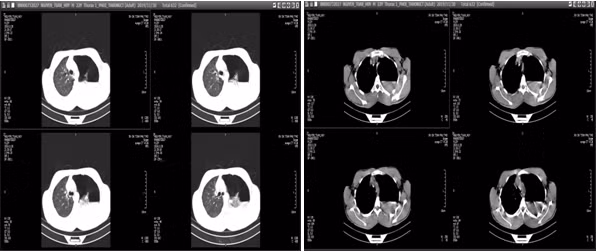

Đước biết trước đó người bệnh khỏe mạnh bình thường và có tiền sử hút thuốc lá 5 năm. Trước lúc vào viện 2 giờ người bệnh đột ngột đau tức ngực trái và khó thở. Người bệnh được chỉ định chụp phim cắt lớp vi tính lồng ngực, kết quả cho thấy: Tràn khí, tràn dịch màng phổi trái.

| Phim chụp cắt lớp vi tính (BVCC). |

BS. Trương Văn Hải - Đơn vị Phẫu thuật Tim Mạch - Lồng ngực - Bệnh viện đa khoa tỉnh Phú Thọ cho biết: Đây là một ca bệnh đặc biệt, hiếm gặp, người bệnh có tràn khí màng phổi tự phát gây xẹp phổi co kéo dẫn đến đứt dây chằng đỉnh phổi chảy máu vào khoang màng phổi.